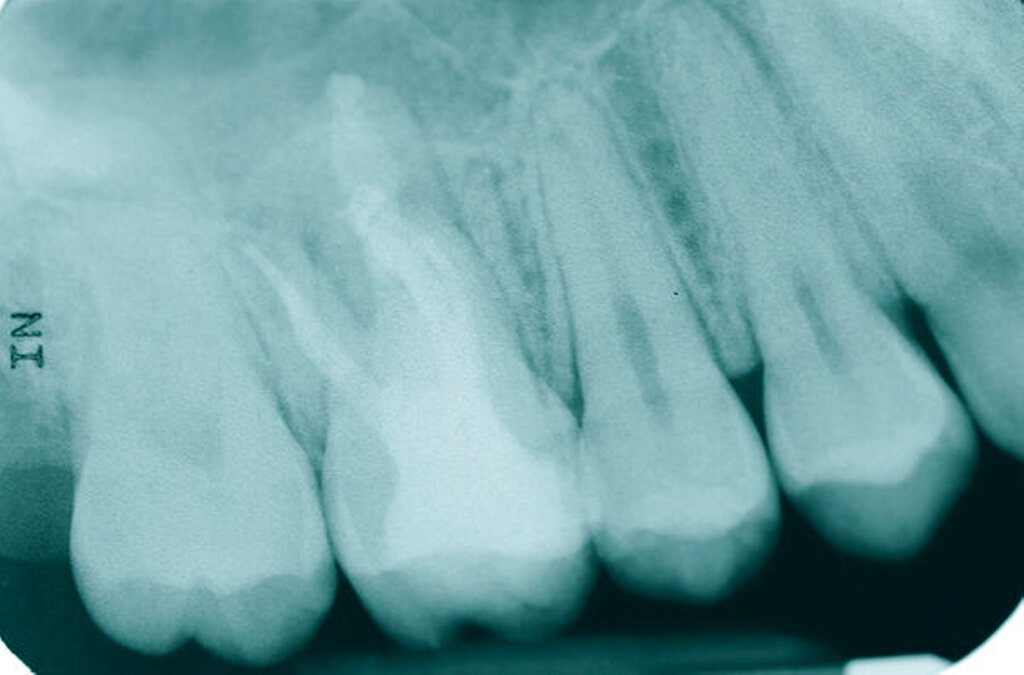

Ein 59-jähriger Patient stellte sich erstmals 2015 mit rezidivierenden pochenden Beschwerden und zeitweise zusätzlich auftretendem Pusaustritt an Zahn 16 vor. Klinisch zeigte sich ein ausgeprägter Attachmentverlust distal mit bis apikal sondierbarer distobukkaler Wurzel, Furkationsbeteiligung und Pusaustritt sowohl über den Parodontalspalt als auch durch einen distobukkal gelegenen Fistelausgang. Zunächst erfolgte die endodontische Behandlung des Zahnes 16 mit anschließender systematischer PA-Therapie. Bei persistierender parodontaler Problematik an 16 wurde die Möglichkeit der Teilamputation der distobukkalen Wurzel mit dem Patienten diskutiert, um die Hygienefähigkeit und damit die Prognose des Zahnes zu verbessern. Auch über die Extraktion als Alternative wurde der Patient aufgeklärt. Er war allerdings motiviert, seinen Zahn so lange wie möglich zu erhalten.

So erfolgte die Amputation der distobukkalen Wurzel mit anschließender Versorgung des Zahnes mittels Vollkrone. Die Situation an 16 ist seitdem für den Patienten subjektiv stabil, die aktuelle Röntgenkontrolle zeigt jedoch eine Progredienz der parodontalen Defekte trotz regelmäßiger UPT und subjektiv guter Mitarbeit des Patienten, was die Prognose des Zahnes negativ beeinflusst. Ursächlich hierfür kann eine persistierende parodontale Infektion durch den trotz Wurzelamputation immer noch schwer für die häusliche Mundhygiene zugänglichen Furkationsbereich mit enger Lagebeziehung der mesiobukkalen und der palatinalen Wurzel sein. Der Patient ist allerdings aktuell mit der Situation zufrieden und beschwerdefrei und wünscht daher noch keine Extraktion des Zahnes, auch wenn diese sich nun fünf Jahre nach dem initialen Befund nicht mehr sehr lange vermeiden lassen wird.